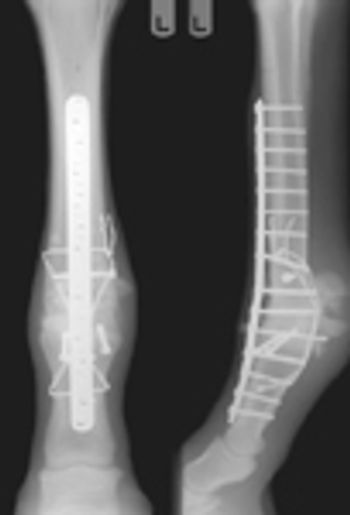

Wounds of the lower limbs of the horse can be challenging to treat successfully, especially those that may involve tendons, ligaments and synovial (joint) spaces.